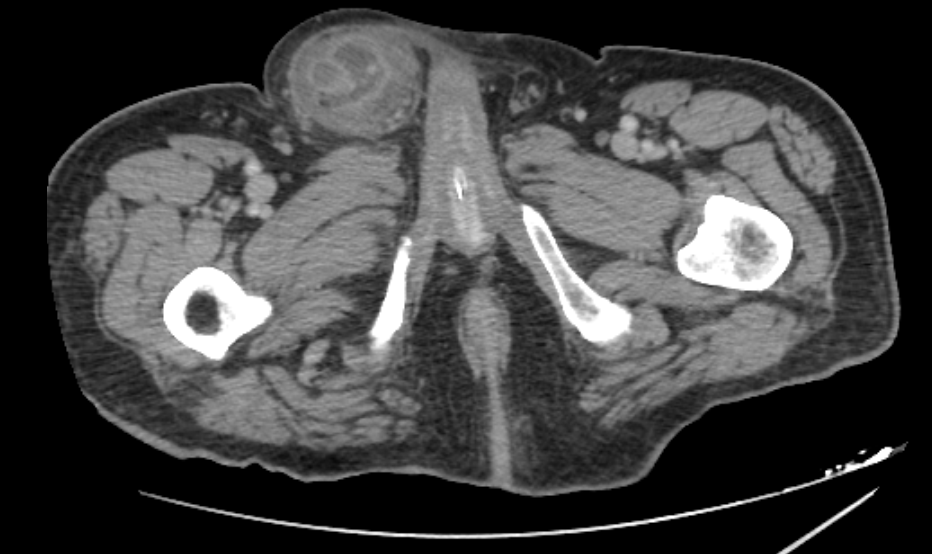

Given the suspicion of a strangulated hernia, surgical intervention was indicated and the patient was taken to the operating room. Under general anesthesia, a right inguinotomy was performed as the initial approach, enabling reduction of the hernial sac’s contents into the abdomen. A subsequent laparotomy revealed an Amyand’s hernia, characterized by the protrusion of the appendix into the hernia sac. The appendix was found to be affected by acute inflammation with gangrene and a microperforation at its apex, which was buffered by the hernia sac itself, configuring a type 2 Amyand’s hernia (figure 4).

Histopathological examination confirmed the diagnosis of gangrenous appendicitis, characterized by transmural necrosis, inflammatory infiltration, and loss of mucosal integrity.

Figure 4